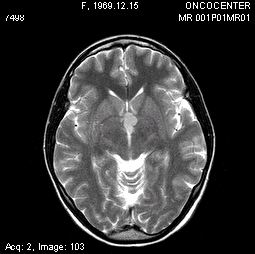

Описываем клинический случай стереотаксической брахитерапии, выполненной в Уральском межтерриториальном нейрохирургическом центре (ГБУЗ СО Свердловский областной онкологический диспансер), пациентке К. 31 год с глиальной опухолью диэнцефальной области (дна III желудочка). Данные МРТ головного мозга представлены на слайдах.

Этапы стереотаксической брахитерапии представлены на слайдах ниже.